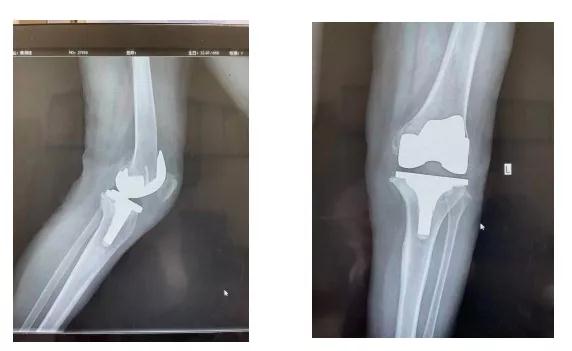

病例二:64岁女性,十多年来左膝关节疼痛、变形,行走困难,多次保守治疗效果不佳,对生活的造成了严重影响,综合评估后,建议患者进行人工膝关节置换,手术置换后患者腿也直了,疼痛也减轻了,生活质量大大提高。

术前 术后